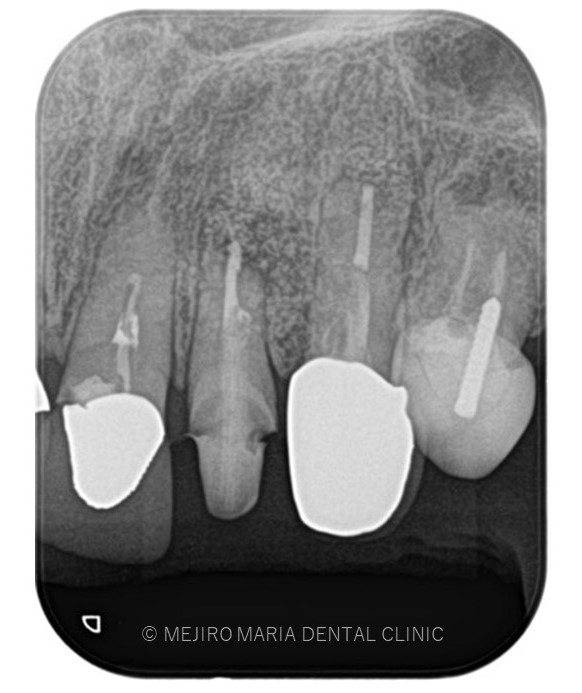

でのリカバリー_該当歯牙の精密根管治療後のレントゲン画像.jpg)

治療詳細